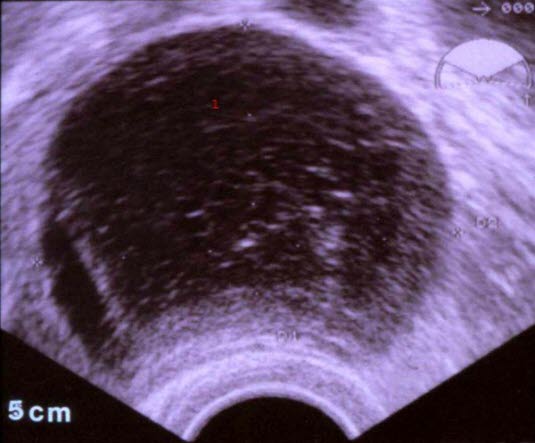

Hemorragisk cyste

1. Hæmoragisk cyste